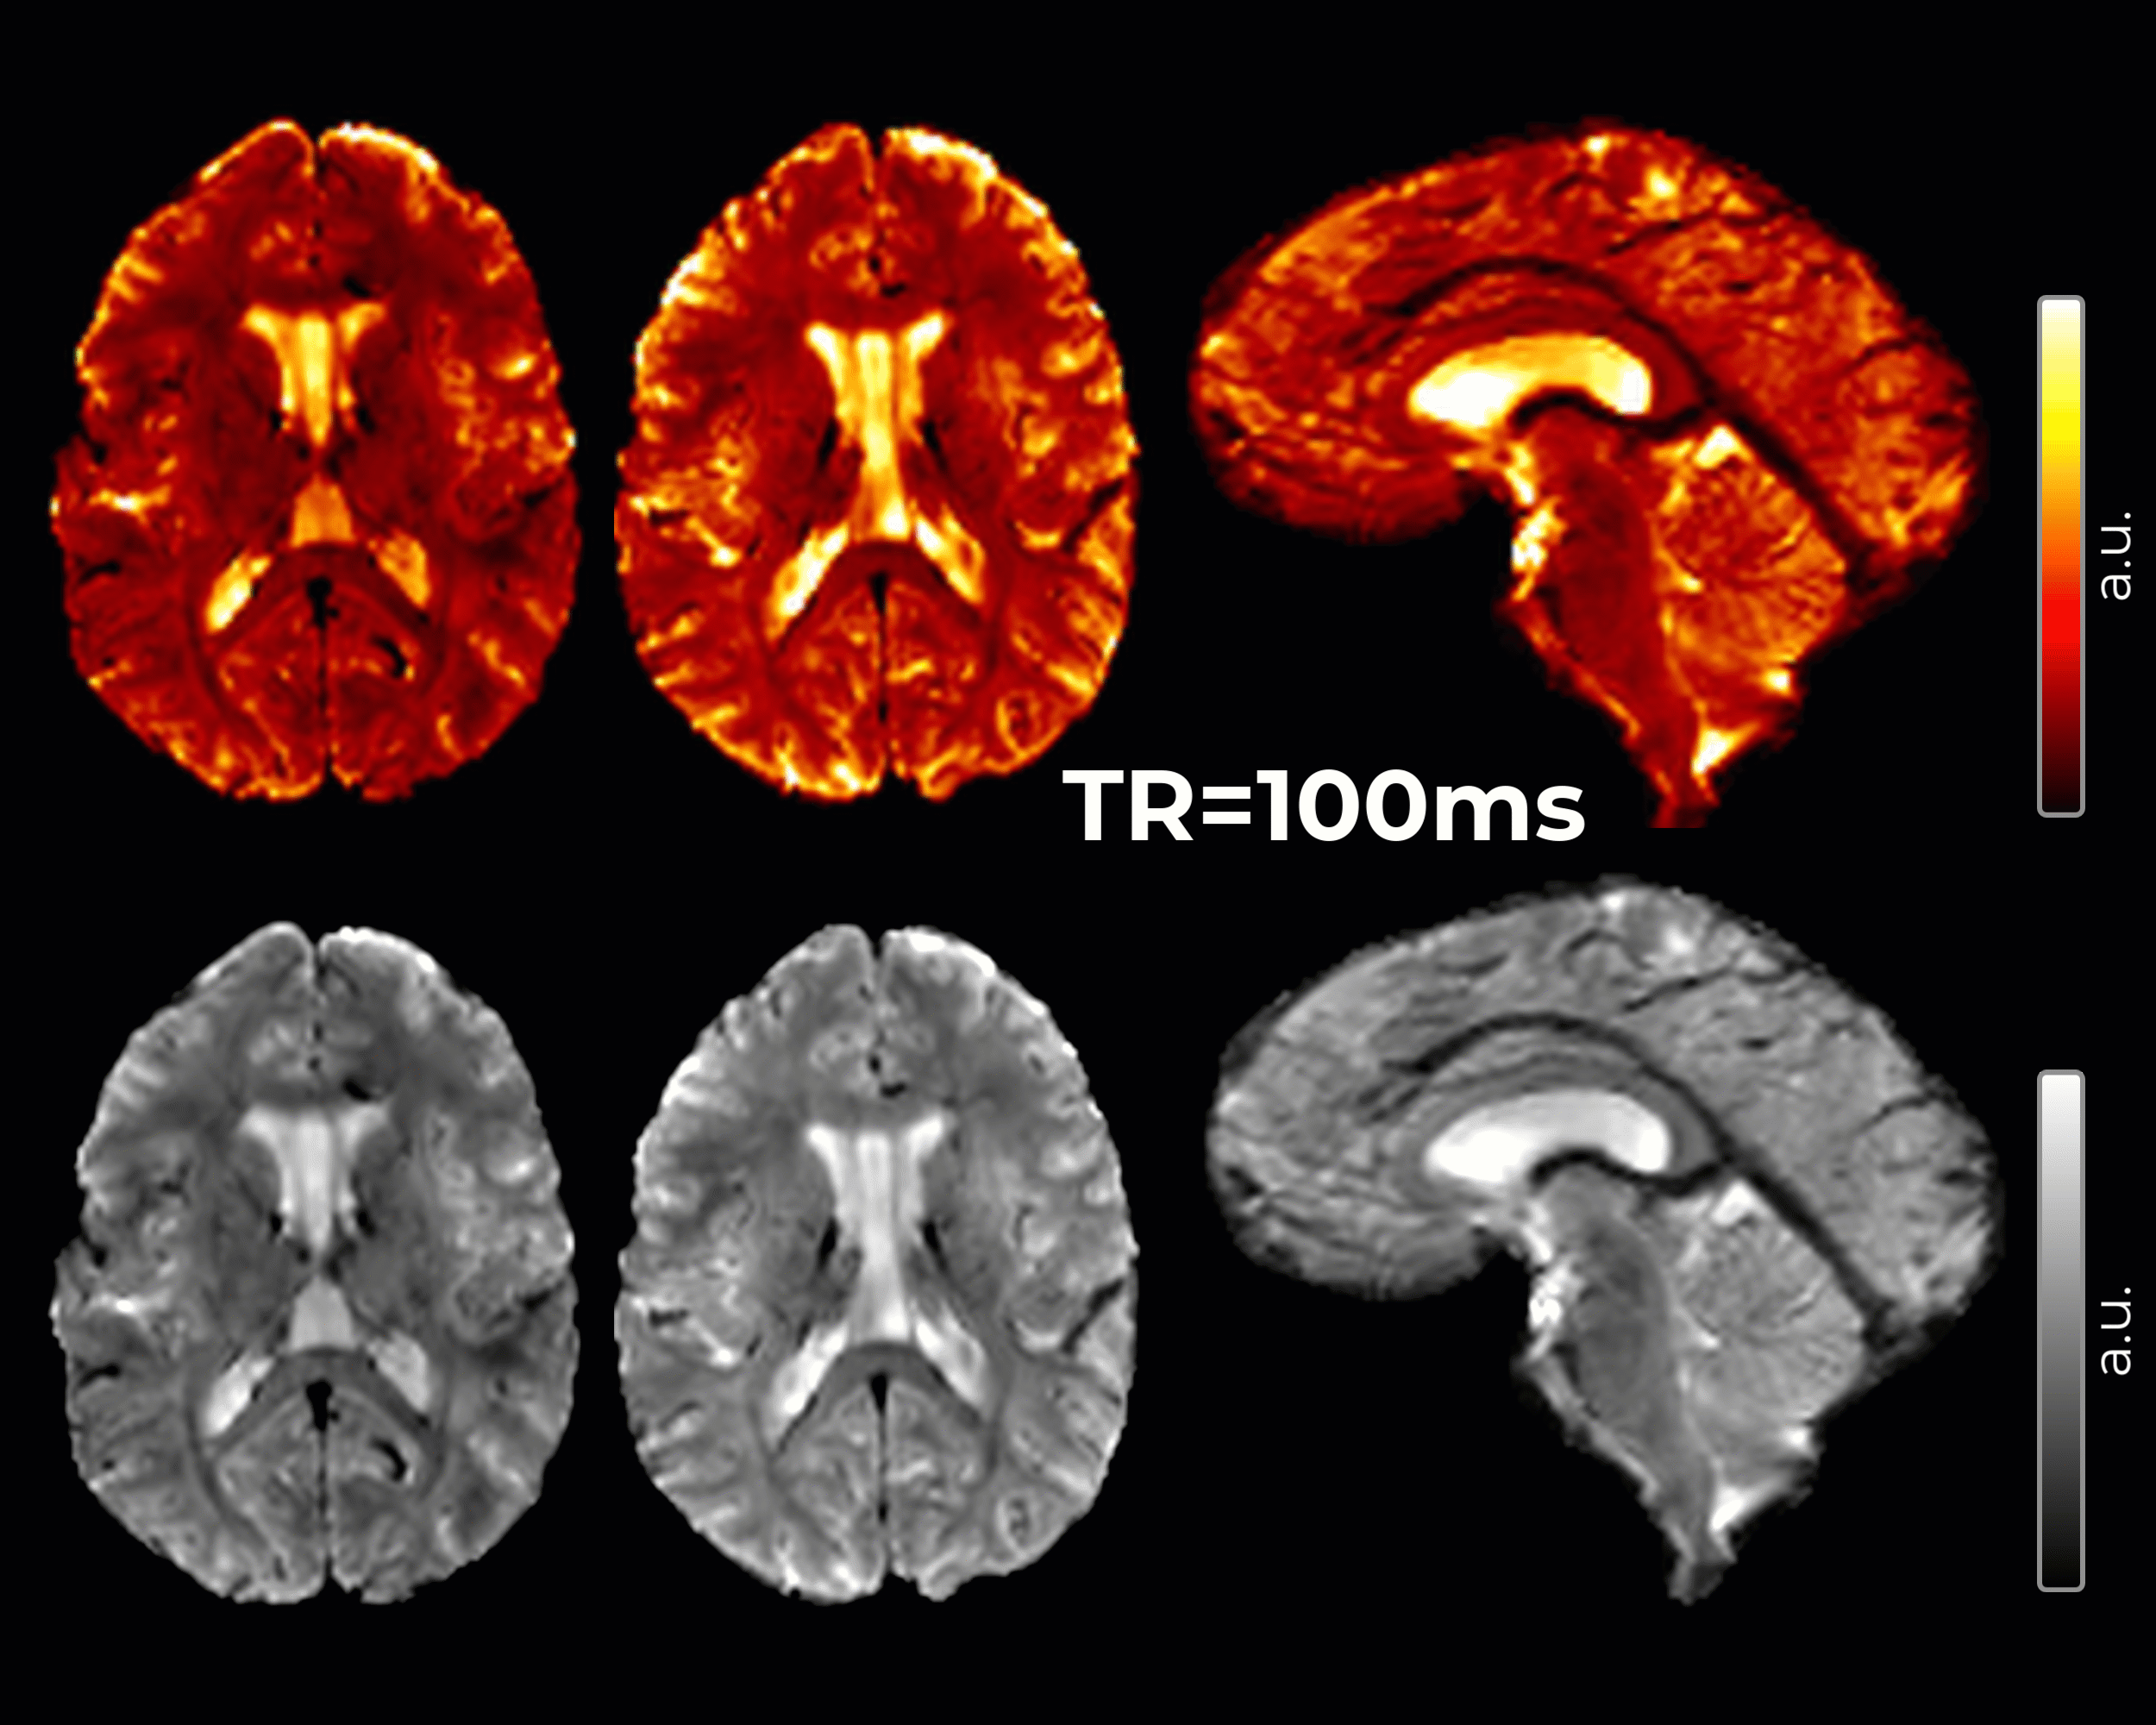

High-Resolution Echo Planar Imaging

The combination of high-resolution echo planar imaging (EPI) and vascular space occupancy (VASO) allows for functional brain mapping and studying cerebral blood volume changes. When a brain region becomes active, there is a decrease in the blood volume and, therefore, a decrease in the VASO signal.

Imaging parameters

- 2 mm isotropic resolution, 60 slices, TE=20ms, TR=1000ms, acquisition time varies based on number of measurements

- 1.5 mm isotropic resolution, 60 slices, TE=20ms, TR=1000ms, acquisition time varies based on number of measurements

- 1.25 mm isotropic resolution, 60 slices, TE=20ms, TR=1000ms, acquisition time varies based on number of measurements

- 0.8 mm isotropic resolution, 60 slices, TE=20ms, TR=1000ms, acquisition time varies based on number of measurements